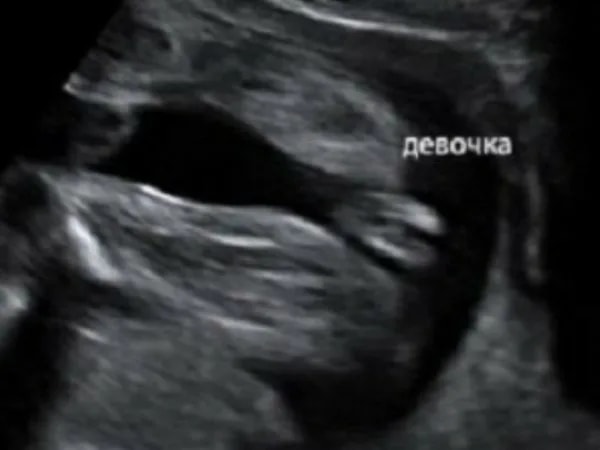

Срок по узи 15 недель и 5 дней. Пол ребёнка?

Девочка скорее всего, а торчит пуповина, если приглядеться пирожочек то видно👌

Тата , разве у девочек пирожок должен так выпирать между ножек?

Светлана , нее выпирать точно не должно, но скорее всего это пуповина🤔

Тата , что то есть 😂 Ну разве может так торчать пуповина?😅 Эх как хотелось избавиться от сомнений и расслабиться… Была уверена в девочке, теперь почти уверена в мальчике, так как уж очень сильно торчит…

Я бы сказала, что девочка. А то, что торчит- это пуповина

Светлана , так у нее и не выпирает- вон, пирожок торчит ☺️ Вам обвели выше. Вы представляете себе малыша в 15 недель? Его размер см 12 наверное. Думаете у него именно это так торчит? Там вообще еще крохотулечка)) Конечно, для убедительности надо бы узи с другого ракурса посмотреть, но я почему-то думаю, что девочка

На мой взгляд, мальчик. Во всяком случае у дочки в 15+3 по-другому выглядело.

Торчит не то, что вы подумали. Я больше склоняюсь, что девочка

Светлана , так это пуповина, кофейное зёрнышко ниже)

Это вообще похоже на пуповину больше, а между ножек все, как у девочек) У меня три девочки, я знаю, о чем говорю😁

Светлана , так там ничего и не выпирает. Для уверенности надо было на узи кровоток включить, если пуповина, было бы видно вены и артерию. Но так чисто визуально - да , пуповина и девочка